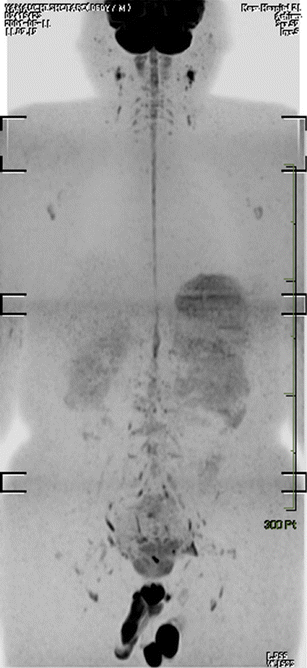

Fig. 4

Coronal maximum intensity projection DWIBS image (inverted black-and-white gray scale) of a healthy 60-year-old male volunteer. Normal high signal intensity (black on this image) can be seen in the brain, spinal cord, nerves of the brachial plexus, prostate, testis, penis, spleen, and cervical, axillary, pelvic, and inguinal lymph nodes